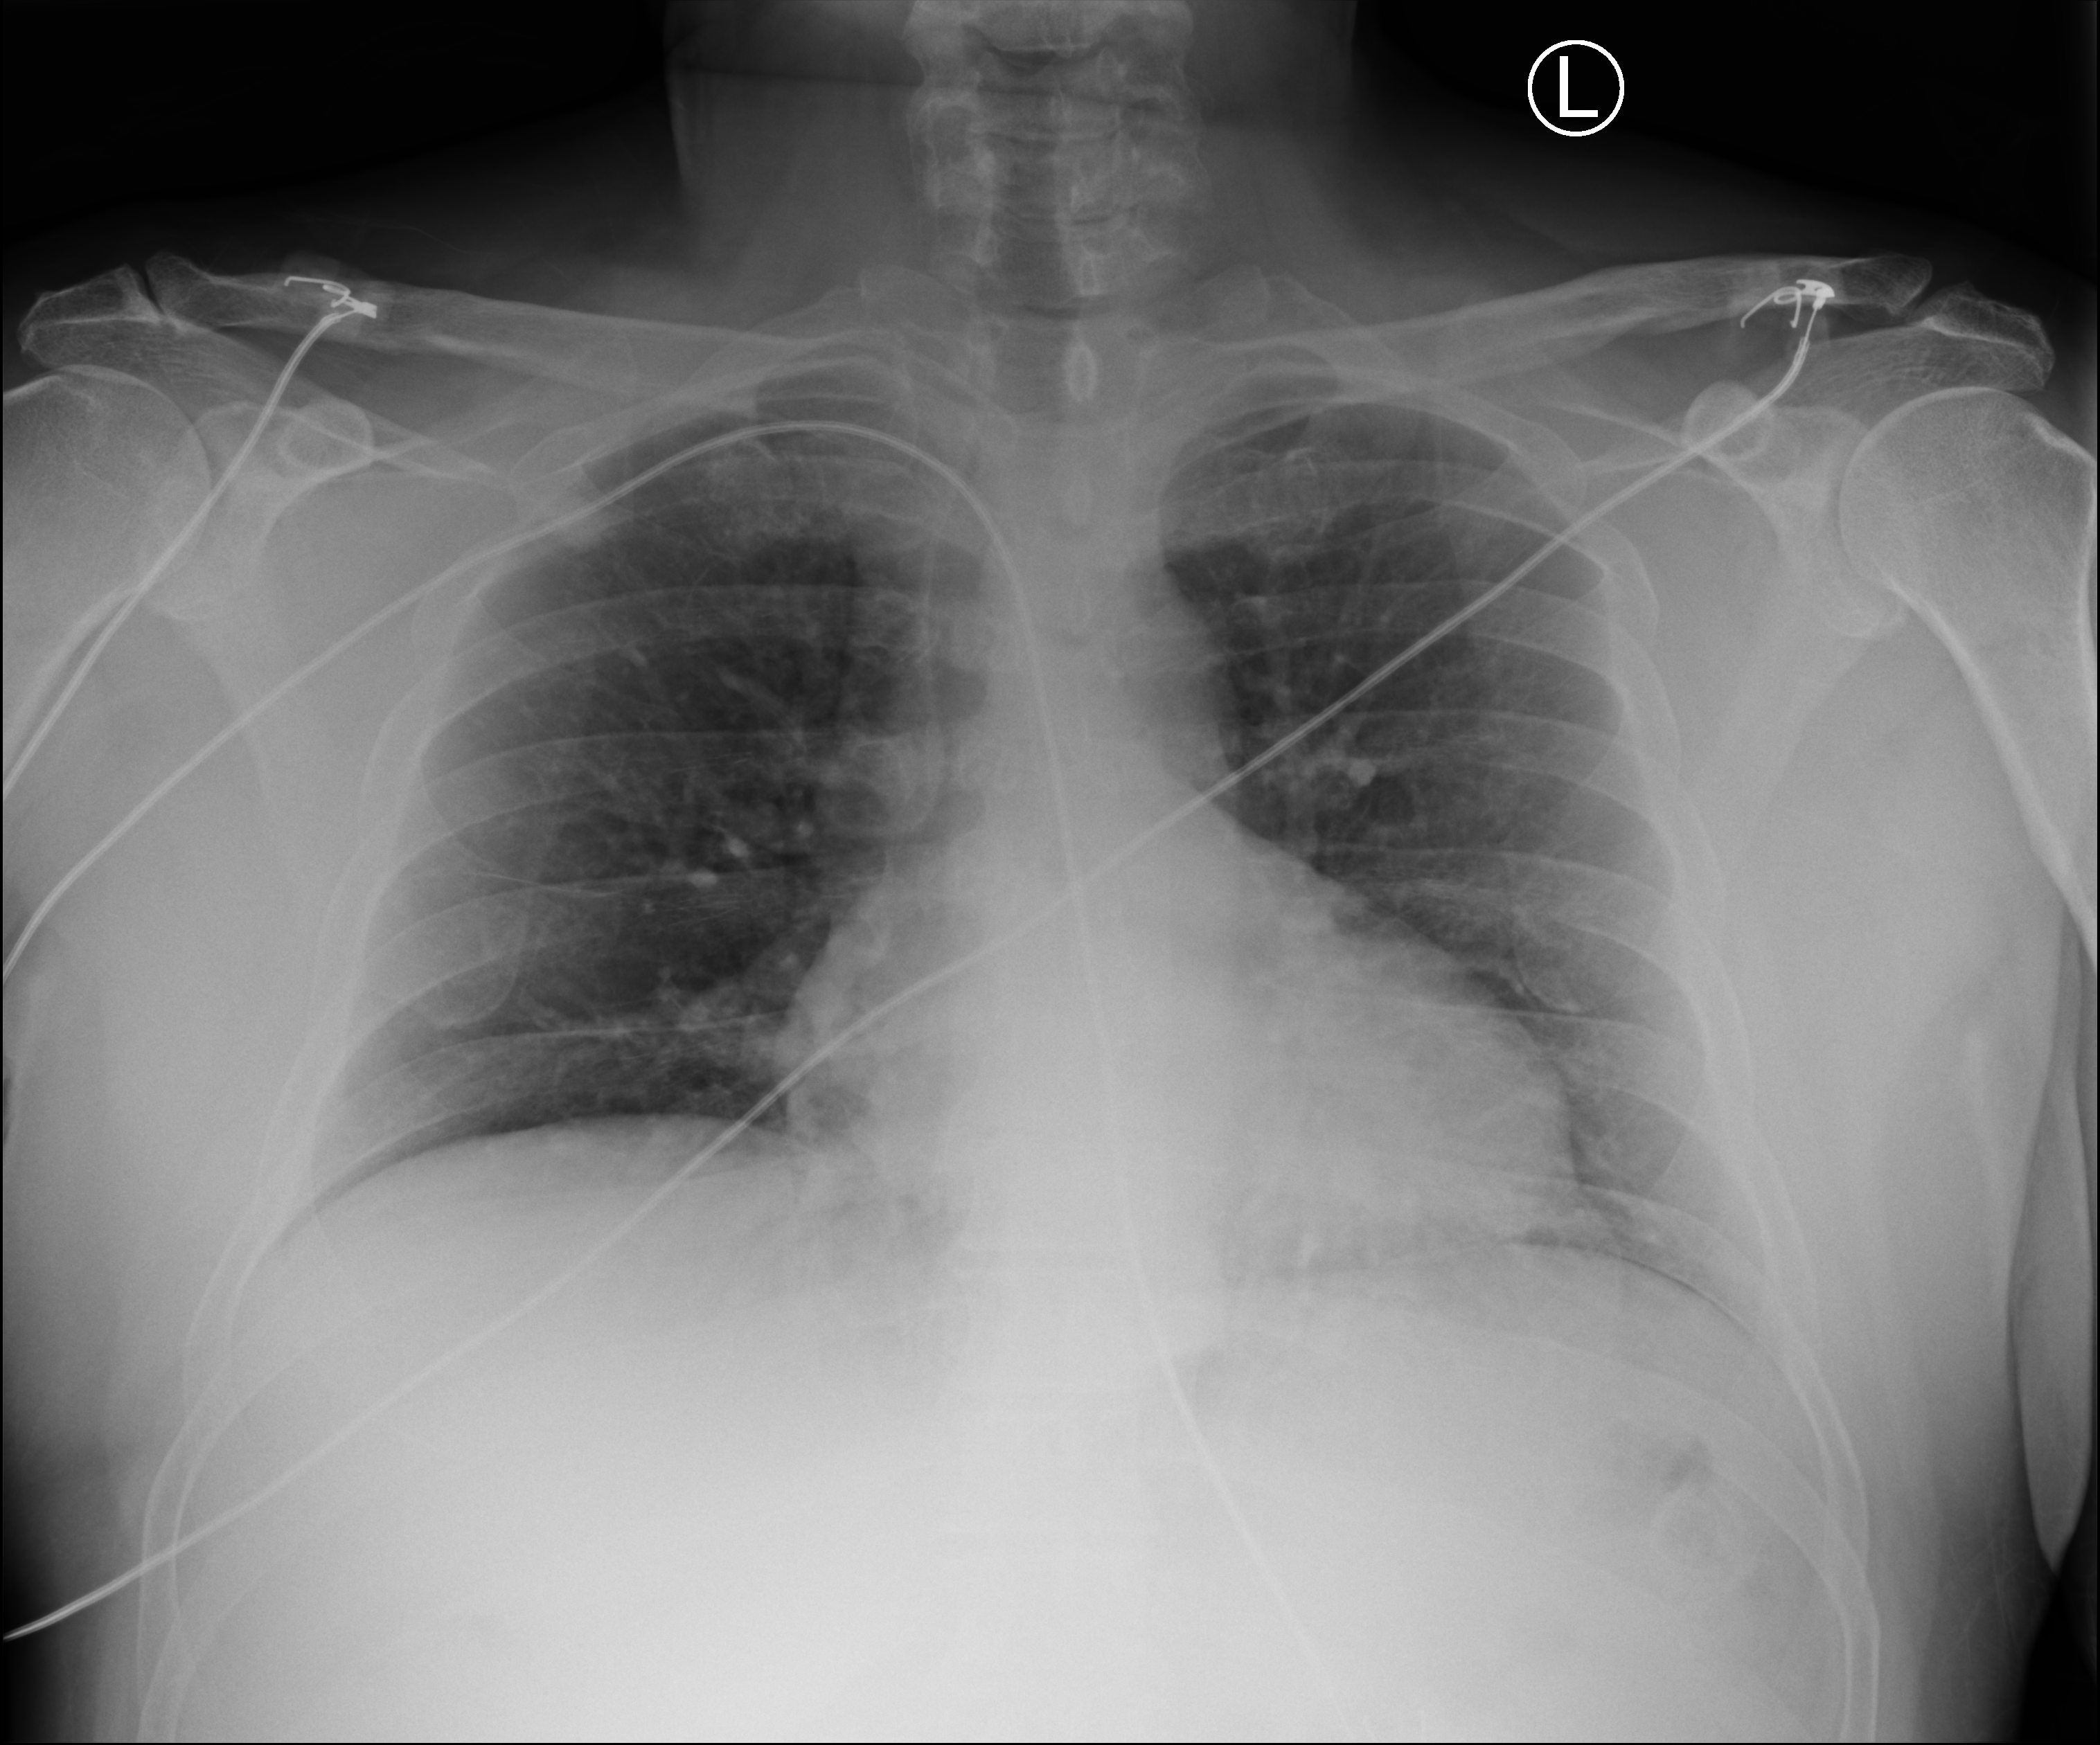

1. The core of each dataset is a large collection of medical images: x-rays, ECG waveforms, digital pathology (and more to come). These rich, high-dimensional signals are too complex for humans to fully see or process—so machine vision can add huge value.